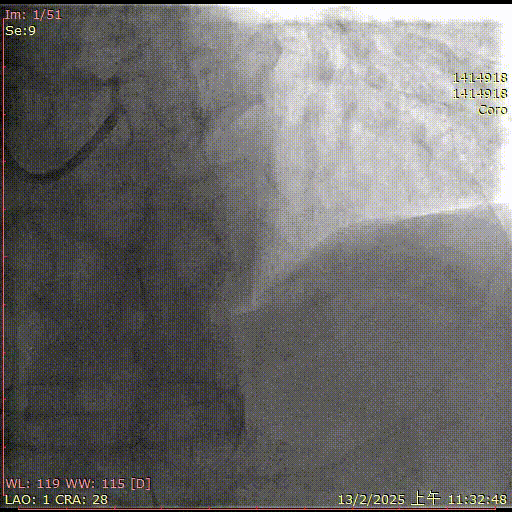

术前造影

术后造影